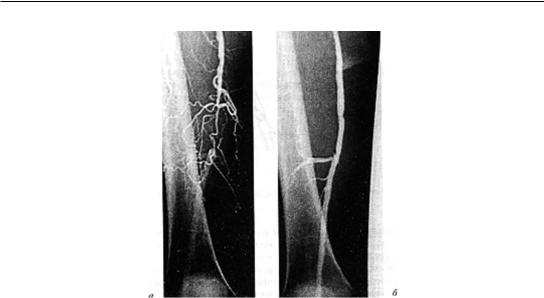

Инструментальные исследования • Дуплексное ультразвуковое ангиосканирование с использованием цветного допплеровского картирования — метод выбора в диагностике тромбоза ниже уровня паховой связки. Основной признак тромбоза: обнаружение эхопозитивных тромботических масс в просвете сосуда. Эхоплотность возрастает по мере увеличения «возраста» тромба •• Перестают дифференцироваться створки клапанов •• Диаметр пораженной вены увеличивается в 2–2,5 раза по сравнению с контралатеральным сосудом, вена перестаёт реагировать на компрессию датчиком (признак, особенно важный в первые дни заболевания, когда тромб визуально не отличим от нормального просвета вены) •• Неокклюзионный пристеночный тромбоз хорошо выявляется при цветном картировании — пространство между тромбом и стенкой вены прокрашивается синим цветом •• Флотирующая проксимальная часть тромба имеет овальную форму и располагается центрально в просвете сосуда • Рентгеноконтрастная ретроградная илиокаваграфия применяется в тех случаях, когда тромбоз распространяется выше проекции паховой связки, поскольку УЗИ тазовых сосудов затрудняется из-за кишечного газа.

Катетер для подведения контрастного вещества вводится через притоки верхней полой вены. Во время ангиографии также возможна имплантация кава-фильтра • Сканирование с использованием 125I-фибриногена. Для определения включения радиоактивного фибриногена в сгусток крови выполняют серийное сканирование обеих нижних конечностей. Метод наиболее эффективен для диагностики тромбоза вен голени.